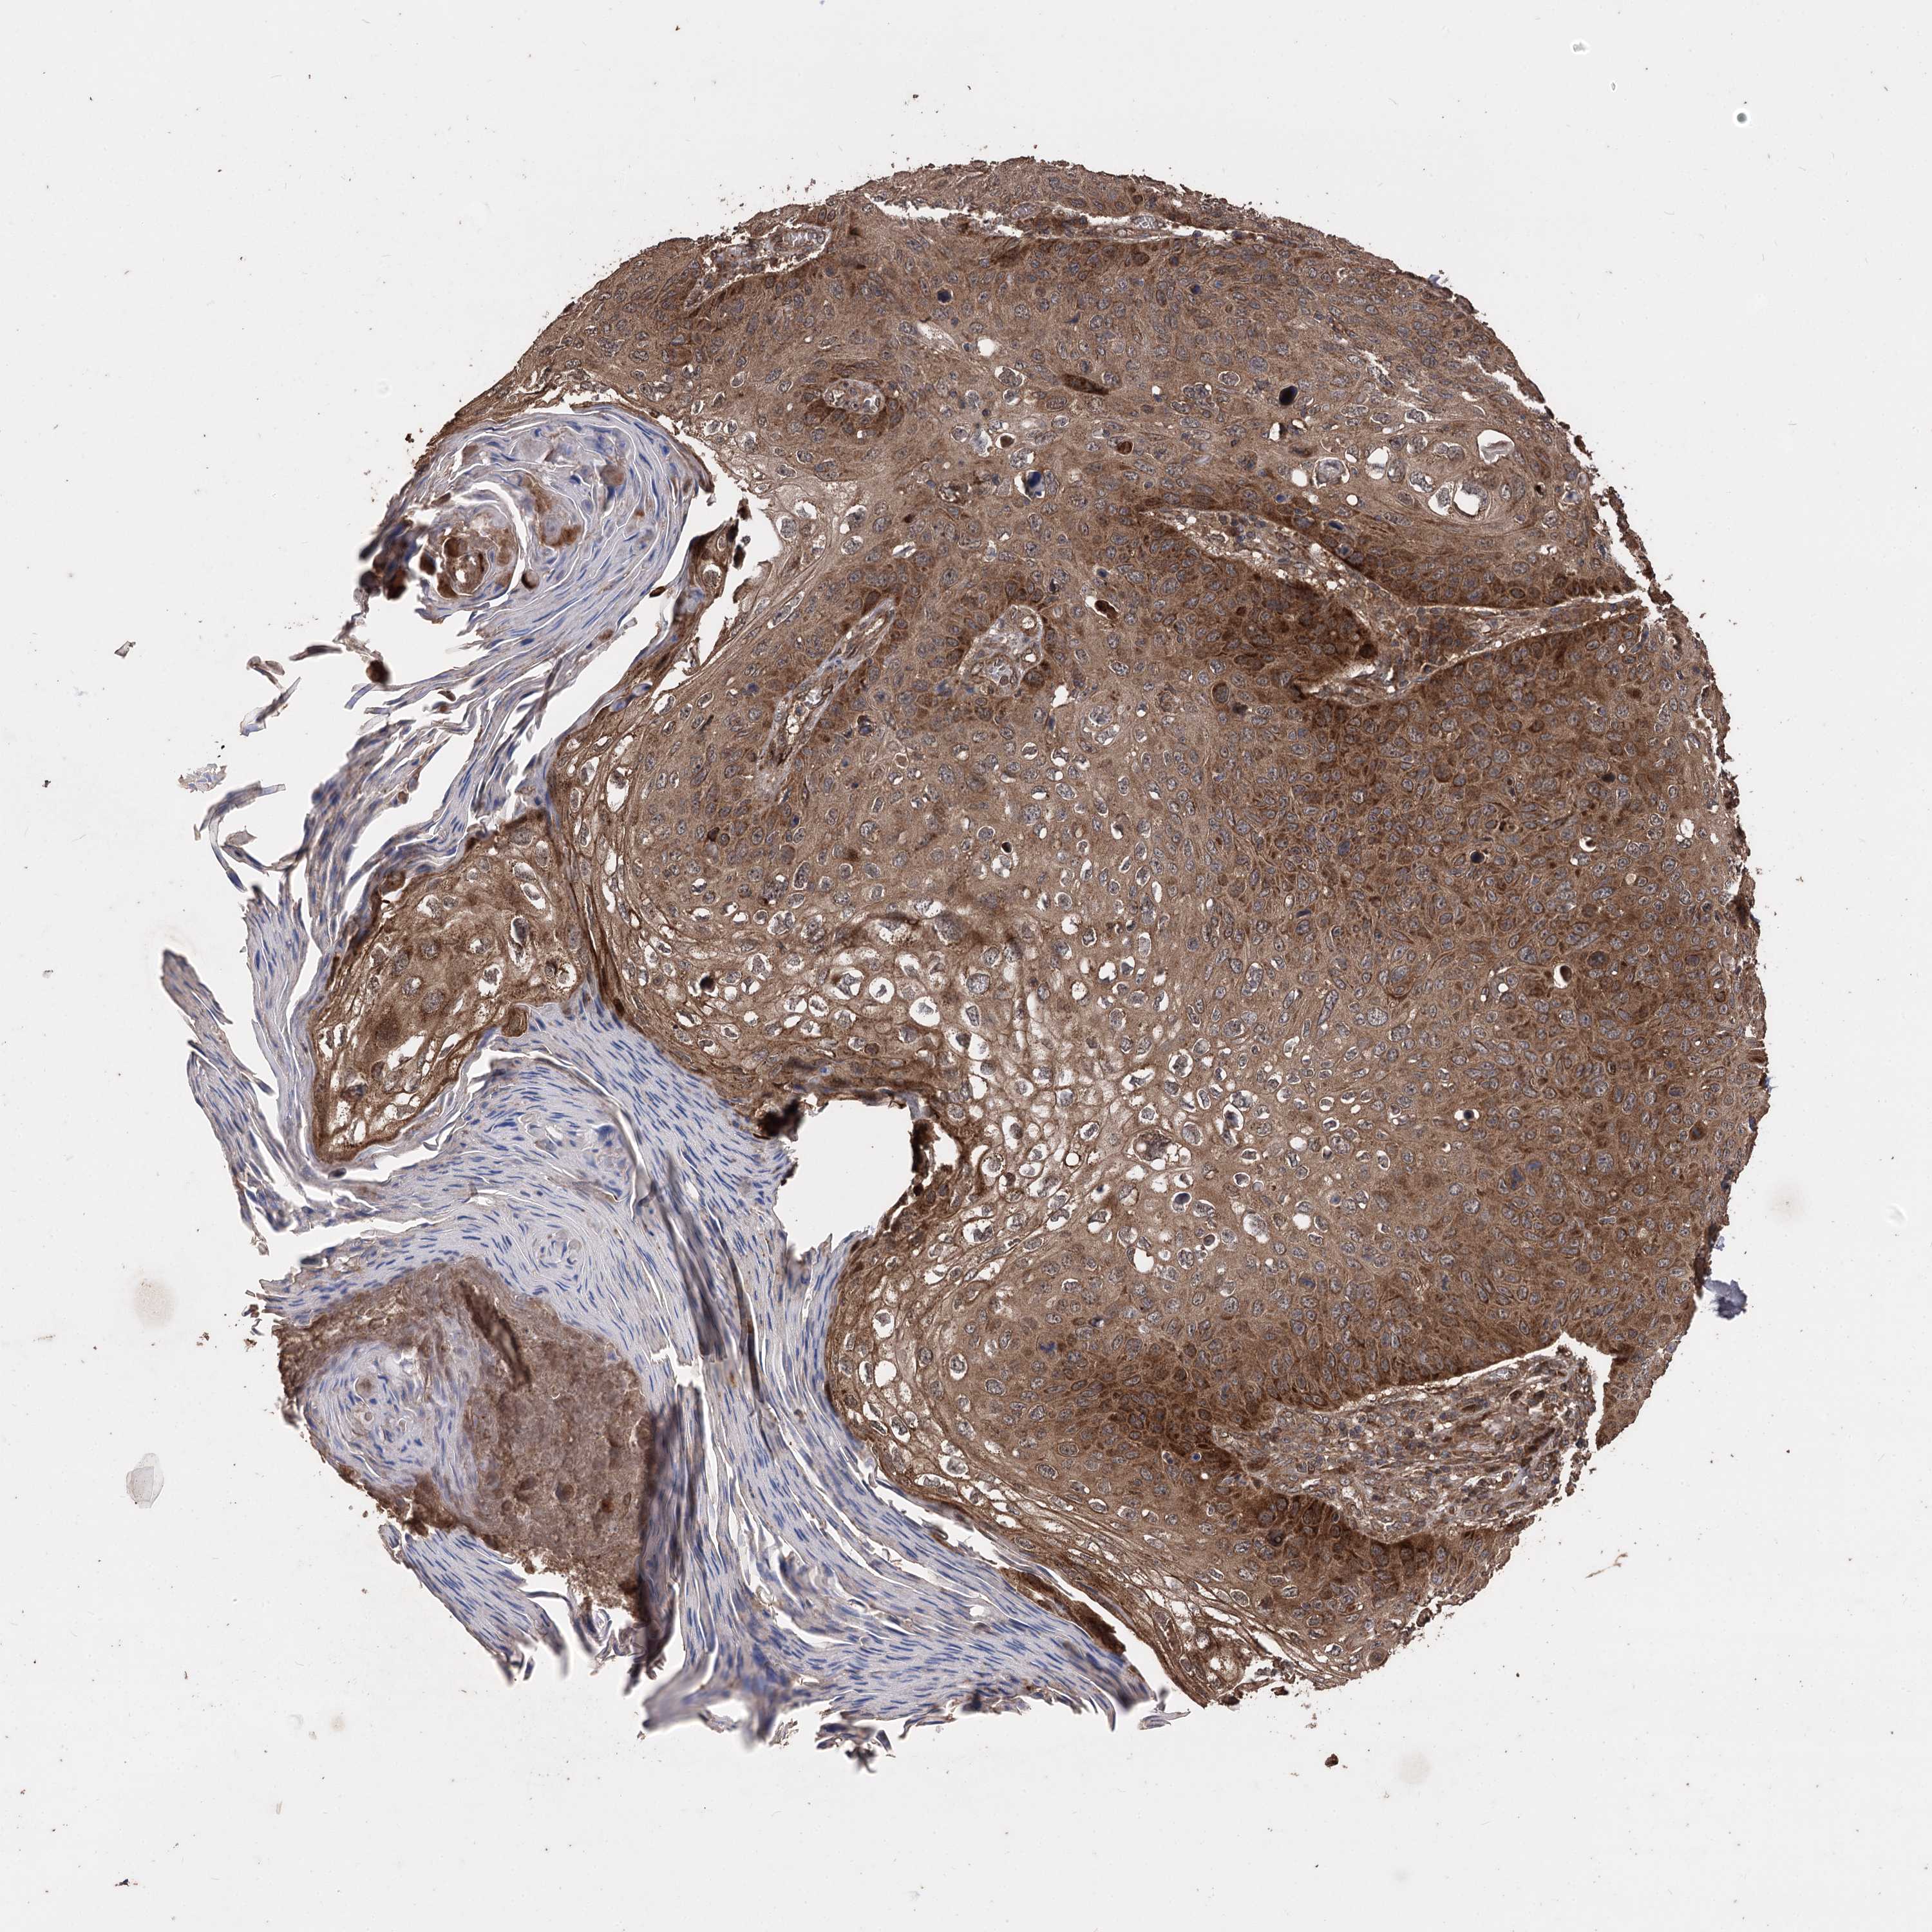

CANCER SKIN CANCER Show tissue menu

Basal cell and squamous cell cancer

SKIN CANCER - Protein expressioni

A mouse-over function shows sample information and annotation data. Click on an image to view it in a full screen mode. Samples can be filtered based on level of antibody staining by selecting one or several of the following categories: high, medium, low and not detected. The assay and annotation is described here.

Antibody stainingi

Antibody staining in the annotated cell types in the current human tissue is reported as not detected, low, medium, or high, based on conventional immunohistochemistry profiling in selected tissues. This score is based on the combination of the staining intensity and fraction of stained cells.

Each image is clickable and will lead to virtual microscopy that enables deeper exploration of all samples and also displays staining intensity scores, fraction scores and subcellular localization as well as patient and tissue information for each sample.

Antibody HPA038469

Antibody CAB022664

Antibody CAB034035

Staining

High

Medium

Low

Not detected

Intensity

Strong

Moderate

Weak

Negative

Quantity

>75%

75%-25%

<25%

None

Location

Nuclear

Cytoplasmic/membranous

Cytoplasmic/membranous,nuclear

Basal cell carcinoma

Squamous cell carcinoma, NOS

Squamous cell carcinoma, metastatic, NOS